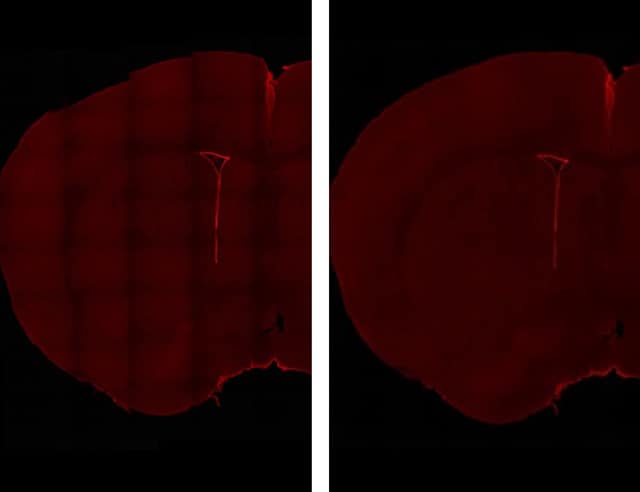

而在已经配备多台显微镜的情况下,研究室又新添了基恩士的荧光显微成像系统BZ 系列。这是因为在决定购买前的演示操作中,这款产品的表现赢得了研究员们的高度评价。示例用途之一,就是脊髓损伤部位的干细胞观察。这项观察必须以低倍率观察脊髓的整体情况。

因为BZ 系列拥有可以在大视野范围内实现高倍观察的样本细节的“图像拼接功能”,这项功能可以自动拼接多张高倍图像,在短时间内拼接出亮度均一的广域图像。可大幅度提高研究效率而备受好评。

“过去,图像合成是一项费时费力的工作,会占用研究员的大量时间。而引进BZ 系列后,原先要耗费2周的实验只需3天左右就能完成。效率提高后,我们就可以重复多次实验,增大n数,进而提高为正确性提供保障的‘再现性’。这在基础领域的研究中显得尤为重要,对我们这些追求真理的科学家而言,BZ 系列能够带来很大的帮助”,冈野先生对引进BZ 系列后的效果进行了如上的描述。

05. 在观察脊髓整体图像时不可或缺的BZ 系列

“在开展未知领域的研究时,我们必须以格外严谨的态度,验证神经细胞究竟是真的发生了再生,还是单纯地表现出了一种特异性现象。为此,必须先用BZ 系列对脊髓等的整体图像进行确认”,冈野先生这样评价道。

作为非常先进的研究室,这里引进了大量精锐的观察设备。即便如此,冈野先生仍表示“引进BZ 系列是很有必要的”。“各大厂商推出了各式各样的高倍率及高分辨率显微镜,但根据我的判断,BZ 系列才是观察细胞整体影像的优秀选择。”

左图为横5张纵8张图像拼接而成的原始数据状态。接缝部分的浓淡不均很明显。

右图则是利用BZ 系列“图像拼接”功能,对图像接缝处的浓淡差异进行自动补正后的图像。基本不会注意到接缝。使用BZ 系列,“图像拍摄及合成、补正所需的时间不会超过3分钟”。

(照片提供:砂堀毅彦先生、庆应义塾大学医学部 助教)